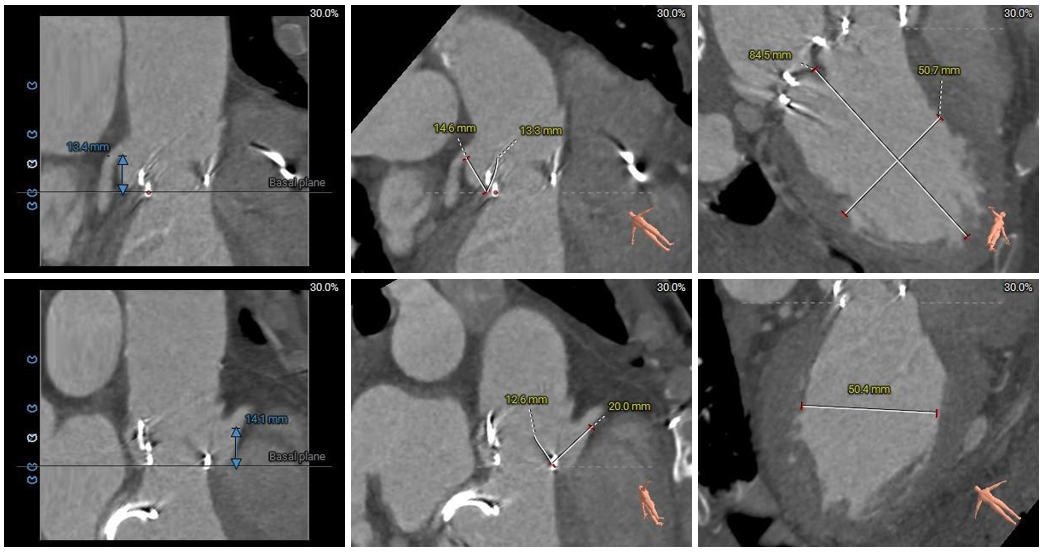

冠脉阻挡风险及左室大小评估

外周血管入路评估